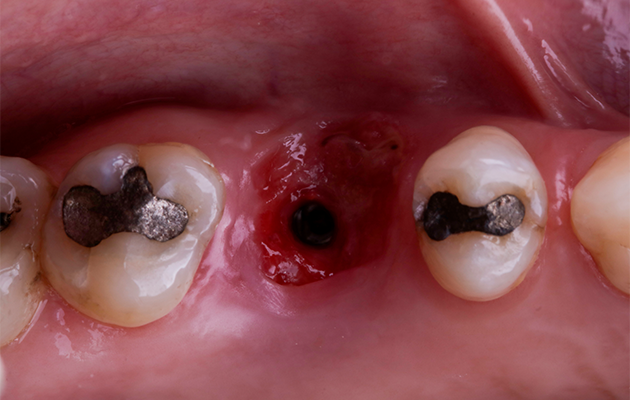

1 | Aspecto inicial do dente 16. Destaque para a supuração drenada via sulco gengival

4 | Vista oclusal mostrando o septo ósseo interradicular preservado após a exodontia